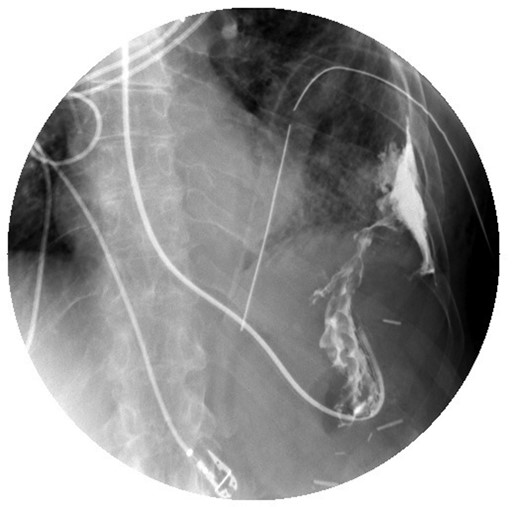

A 69-year-old female with Stage IV ovarian cancer status post-total abdominal hysterectomy, bilateral salpingo-oophorectomy, appendectomy, tumor debulking and eight cycles of carboplatin and paclitaxel presented with sudden onset of dyspnea. She reported a 4-month history of mild dyspnea and pleurisy, which had been attributed to previously diagnosed, cytology-proven bilateral malignant pleural effusions. She was also being treated for bilateral lower extremity Deep venous thromboses with warfarin. Computed tomography (CT) chest demonstrated a left hydropneumothorax with mediastinal shift (Fig. 1). Thoracostomy tube was placed with tea-colored drainage on insertion. She was intubated the following day for respiratory failure.

CT chest demonstrating left hydropneumothorax with mediastinal shift.